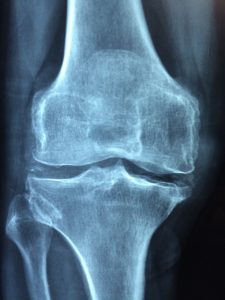

ניתוח להחלפת מפרקים עשוי להיות החלטה קריטית שתשנה את חיים לטובה. ככל שהאפשרות להחלפת מפרקים מותאמת אישית קיימת לשמחתנו, לפני כל ניתוח כזה, חשוב יותר

שחיקת סחוס, או בשמה הרפואי – אוסטיאוארתריטיס של הברך, הינה בעיית ברכיים נפוצה אשר סובלים ממנה אנשים רבים. מחקרים הוכיחו כי בערך כשליש מן האנשים